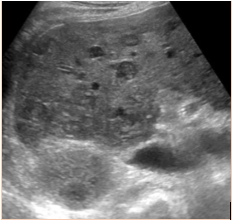

Abstract: We report a case of a 34 year old male with AIDS who presented to the hospital with abdominal pain and dyspnea. He received a comprehensive work-up including extensive imaging and biopsies revealing high grade mature B-cell lymphoma with features consistent with Burkitt’s Lymphoma with concomitant Ebstein Barr viremia. This case demonstrates the need for vigilance when assessing patients with HIV or AIDS for lymphoma with vague complaints and no identifiable source of infection.References